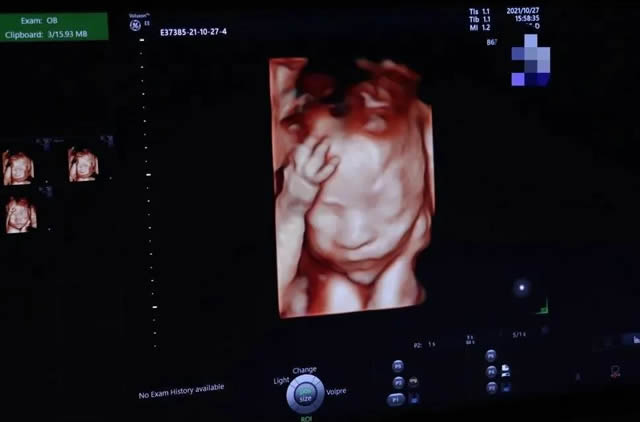

羊水對於胎兒來說可謂至關重要,它就像胎兒的(de)保護罩,不(bú)僅可以(yǐ)幫助胎兒緩和孕媽腹部外(wài)來的衝擊,還可以為胎兒形成相(xiàng)對溫(wēn)和的環境供寶寶成長,維護胎寶寶的健康發育。...